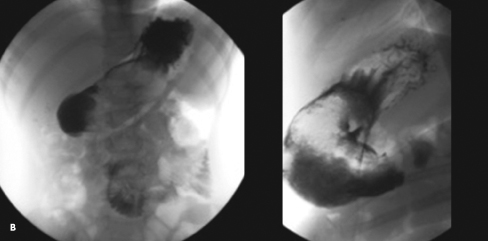

A plain abdominal radiograph revealed a mottled density over the gastric body and antrum (A). Findings on ultrasound examination suggested a few scattered lymph nodes in the periumbilical area and right lower quadrant. An upper GI barium study showed filling defects in the gastric body and proximal jejunum, which were highly suggestive of a trichobezoar, considering the history (B). During exploratory laparotomy with gastrotomy and jejunotomy, 3 trichobezoars were removed (C).

Diagnosis of bezoars requires a high index of suspicion because the presentation is often vague and misleading. The mass can be suggested on plain radiographs, barium studies, and CT scans. The characteristic finding on an abdominal CT scan is a nonhomogeneous, nonenhancing mass in the lumen of the stomach or small bowel.4 Tiny air pockets within the mass may give it a mottled appearance, simulating small bowel obstruction.7 Oral contrast circumscribes the mass and may fill the interstices near the surface.